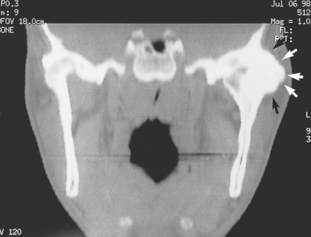

The pathology of this condition is described in pathology texts, but it is worth reminding readers that ankylosis is the physical union of two bones that normally are partners in a movable joint. The union may be partial or total and either fibrous or bony (Fig. 17.7). In the TMJ the cause may be trauma (especially intracapsular fractures), infection or a systemic arthropathy such as juvenile rheumatoid or reactive arthritis.

image

Fig. 17.7 CT scan showing ankylosis of the TMJ. An extensive mass of bone (arrows) extends around the lateral aspect of the left joint and the joint space is not visible. There is also loss of joint space in the right joint.

The principal clinical feature is severe restriction of mouth opening (no more than a few millimetres). The onset may be traced to a particular event (infective or traumatic) or it may be slowly progressive. In either event there is no relief. Investigation should include CT and/or MR imaging as well as conventional radiographs to determine the bone relationships (not only in the joint but also between the coronoid process and the zygomatic arch, maxilla and squamous temporal). Care should be taken to exclude muscular causes of limited opening and the rare hysterical reactions which do not derive from the joint at all.